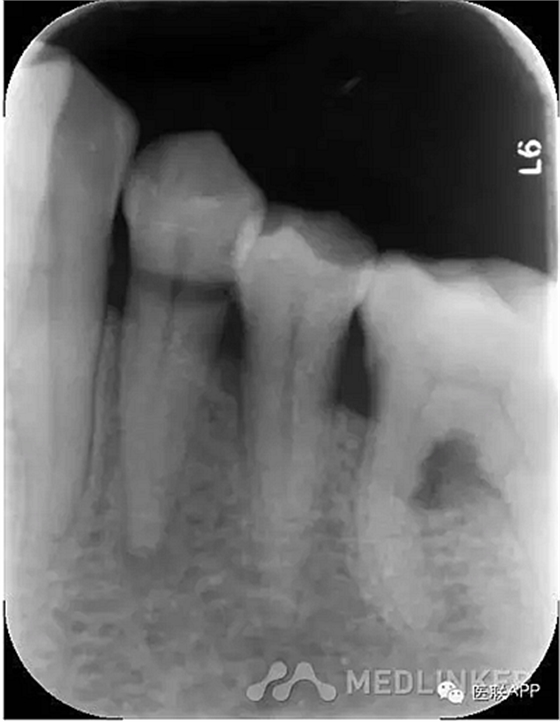

34頰側(cè)楔狀缺損達髓腔,可探及穿髓孔,探痛(-),叩痛(+),松動I度。

X線示:34根尖周小面積低密度影。

診斷:34慢性根尖周炎